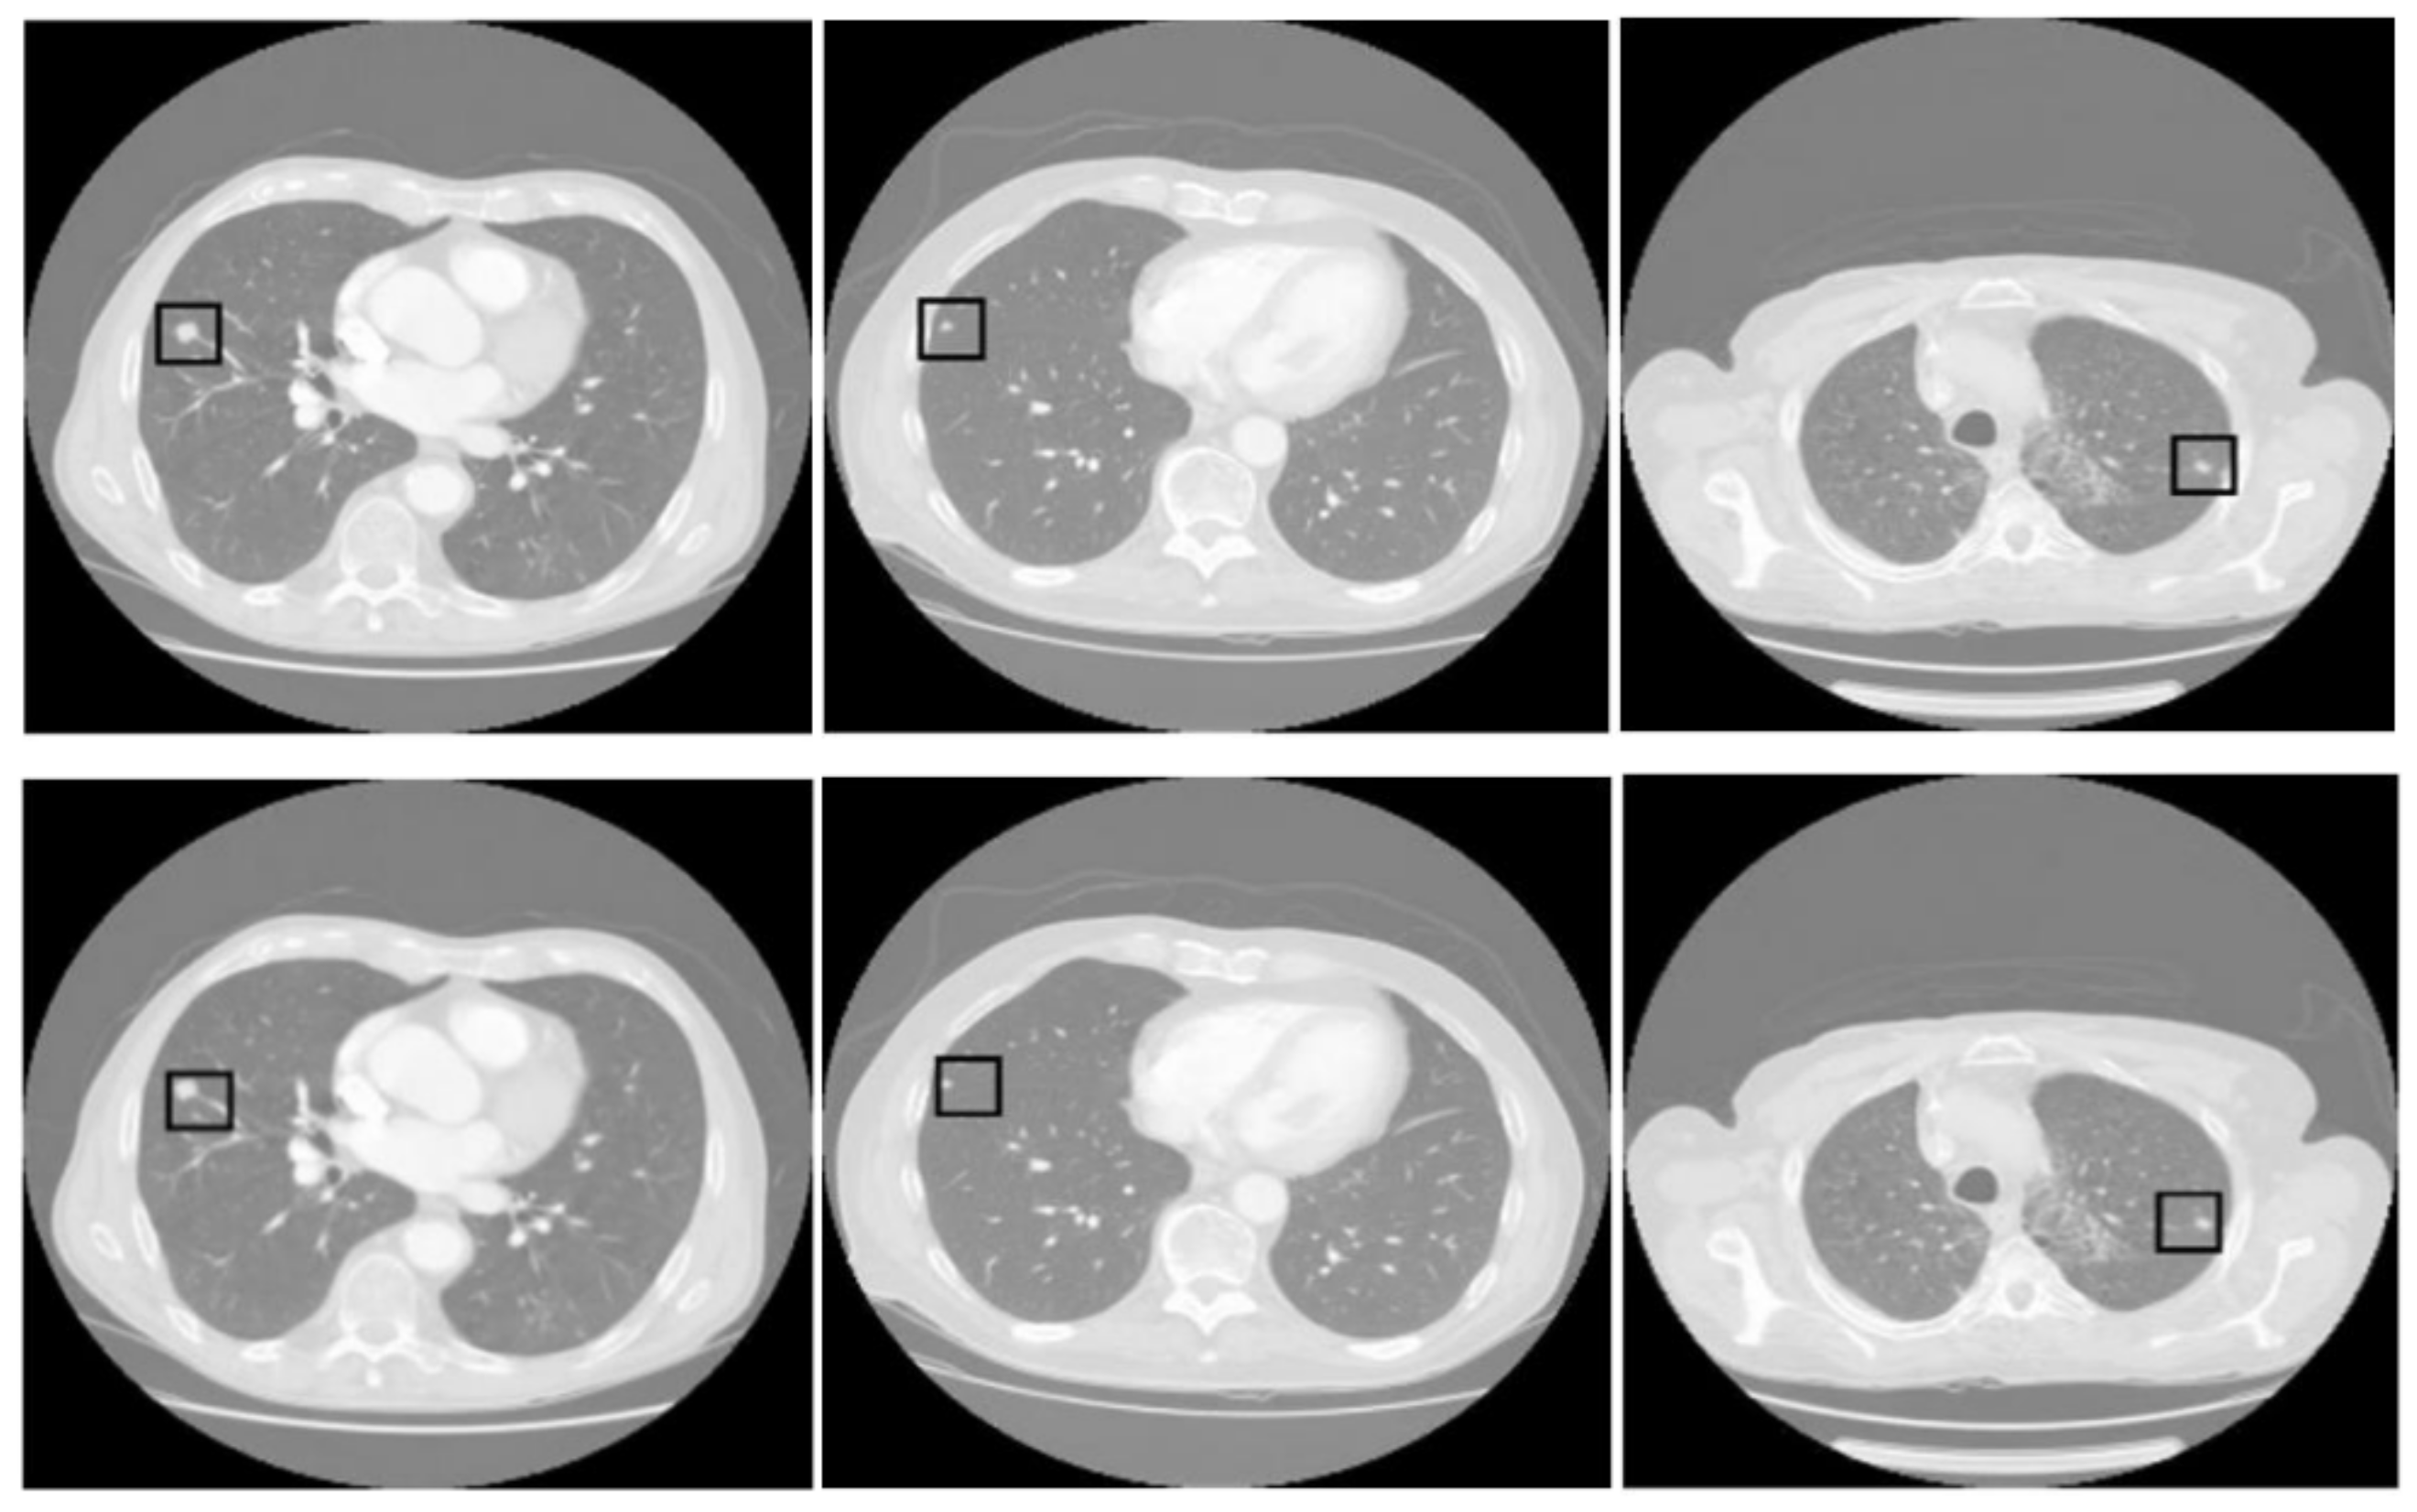

Figure 5 presents three pairs of images generated by the proposed tumor detection model, where the ground truth annotations are displayed in the top row, and the outputs of the model are shown in the bottom row. A collective analysis of these images suggests that the proposed model demonstrates a commendable level of precision in pinpointing the location of lung tumors. Across the set, the regions marked by the model align well with the ground truth indicators, denoted by squares. This alignment indicates that the model has successfully learned to identify the critical features of lung tumors from CT scans and can consistently distinguish tumor tissue from surrounding anatomical features.

Figure 5.

Comparative analysis of tumor detection. The top row shows the ground truth, while the bottom row presents the model predictions. The black square in every sample shows the tumor extracted by the proposed model.